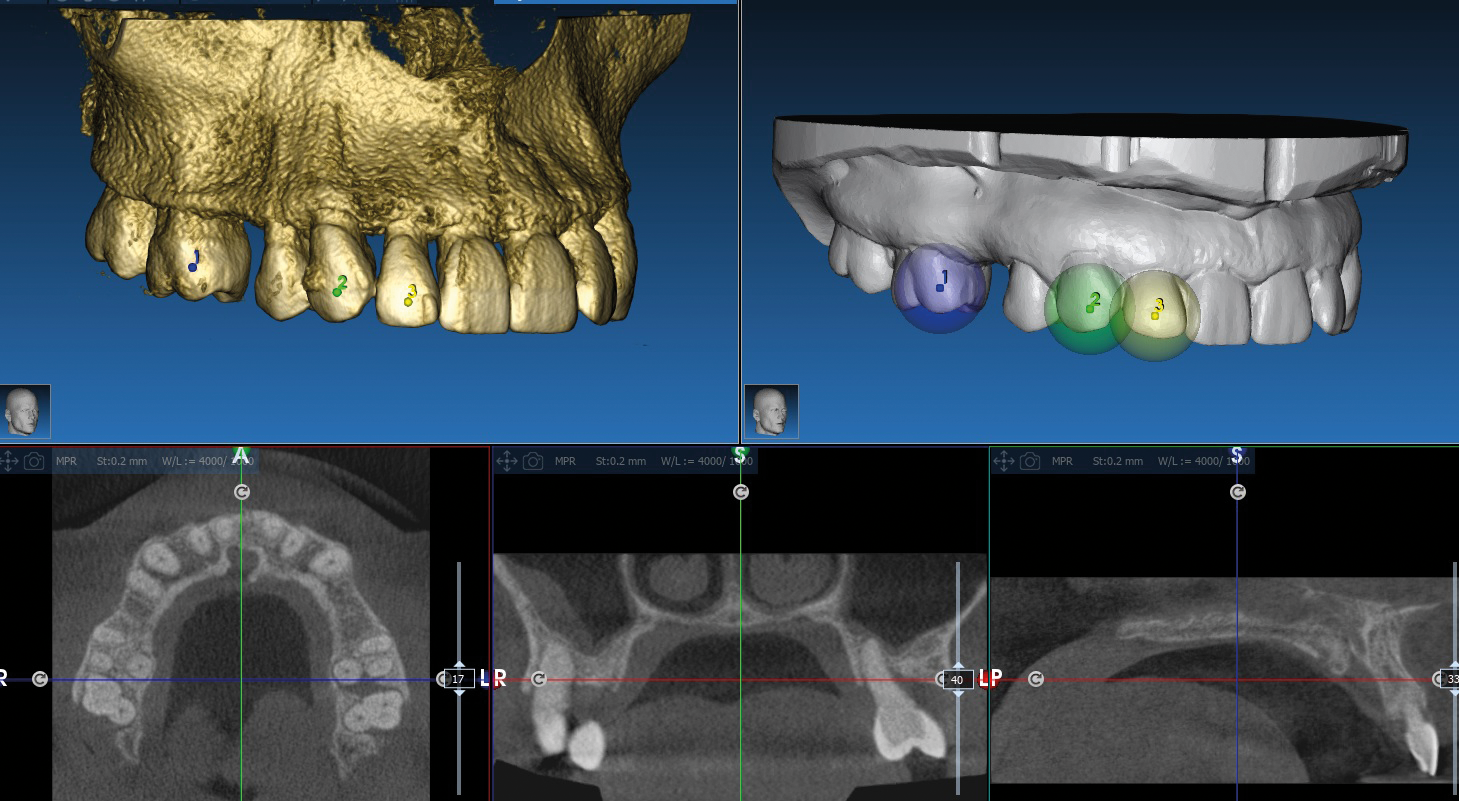

X-ray diagnostics and planning

A Dicom 3.0 file is created with the double scan technique (CT/DVT). Likewise, the current scon prosthesis alone is recorded and digitised In the case of residually toothed, not heavily restored jaws the double scan technique can be dispensed with.

The data thus obtained is then read into the ICХ-МАGELLAN 3D planning software. When the planning of the implant positions in the 3D software is completed, the data for setting the positioner iscalculated.